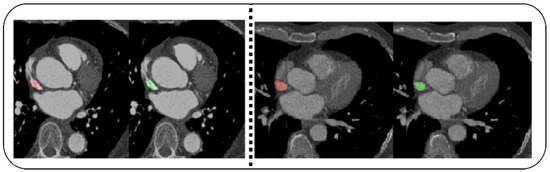

- Demirer, M.; Gupta, V.; Bigelow, M.; Erdal, B.; Prevedello, L.; White, R. Image Dataset for a CNN Algorithm Development to Detect Coronary Atherosclerosis in Coronary CT Angiography. Mendeley Data, V1. Available online: https://data.mendeley.com/datasets/fk6rys63h9/1 (accessed on 2 November 2021).